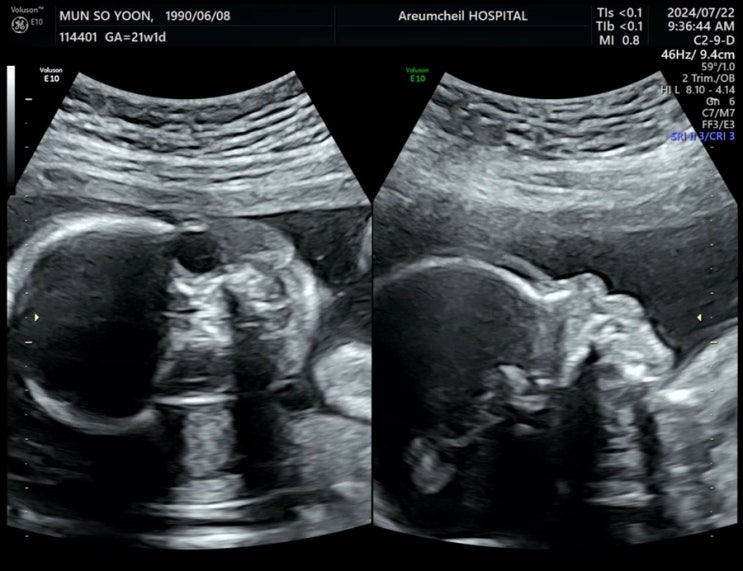

임신 21주 -24주 : 정밀초음파, 태동, 젤리캣 인형, 그리고 임당 검사를 기다리며

임신 21주 "정밀초음파" : 아기 태동은 언제부터 느낄수 있는 것일까? 20주부터 태동을 슬슬 느...